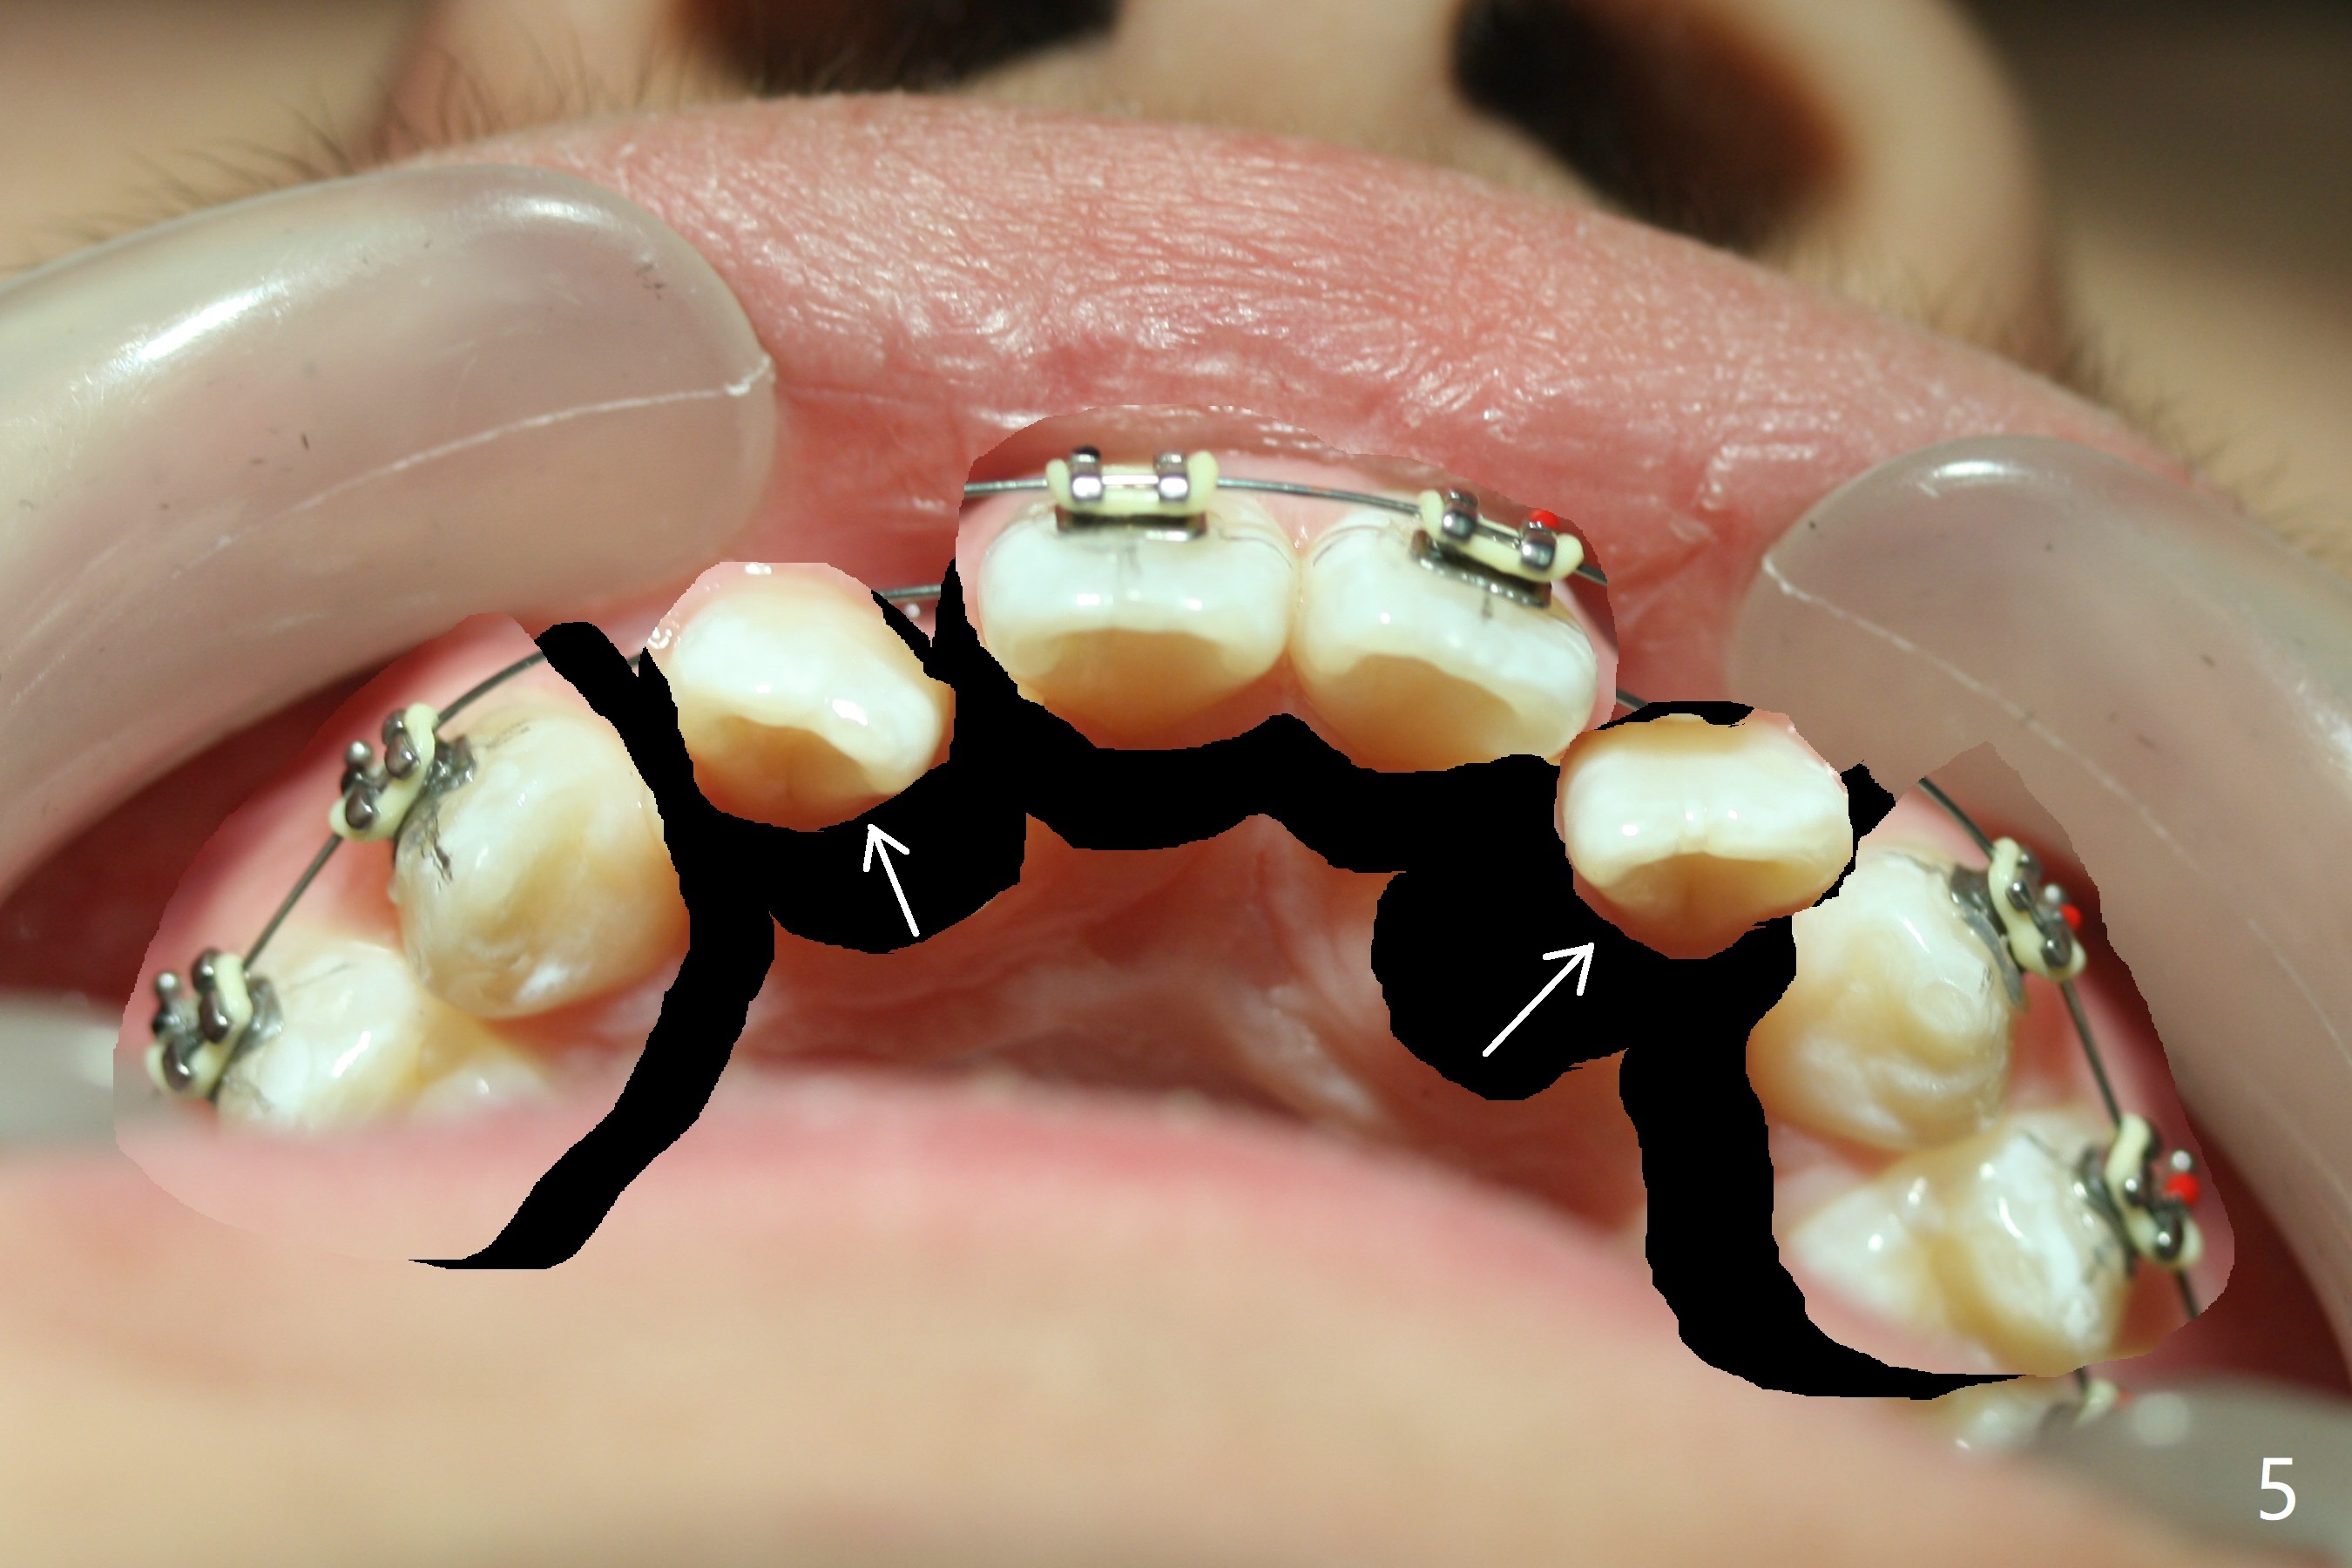

Cephalometric analysis shows Class III skeletal relationship. The roots of the upper anterior teeth (Fig.1,3 *) are prominent before treatment. In order to correct the cross bite of U2s (Fig.2,5), the upper arch needs expansion (Fig.4). Will the arch expansion cause buccal plate loss of the upper teeth? The upper dental midline matches the lower one by using the left open coil spring only (4 months 10 days post banding, Fig.6).